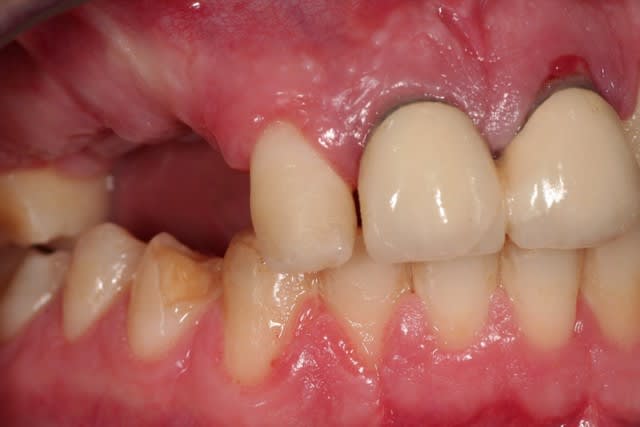

> la 22 est très enfoncée dans son alvéole, elle

> n'est pas fracturée, et silencieuse cliniquement.

> je pensais tricher avec une facette. mais je vais

> avoir un souci de ligne de collet.

si jamais tu decides de garder les laterales,envoie des retros:sur la pano,luxation sur la 12?la 22 intrusee?pas assez clair

Si tu avais une photo du sourire, des dents antérieures de face et des rétroalvéolaires des incisives supérieures, ce sera sympa. D'autre part, la 22 a-t-elle un son normal à la percussion ? Merci d'avance.